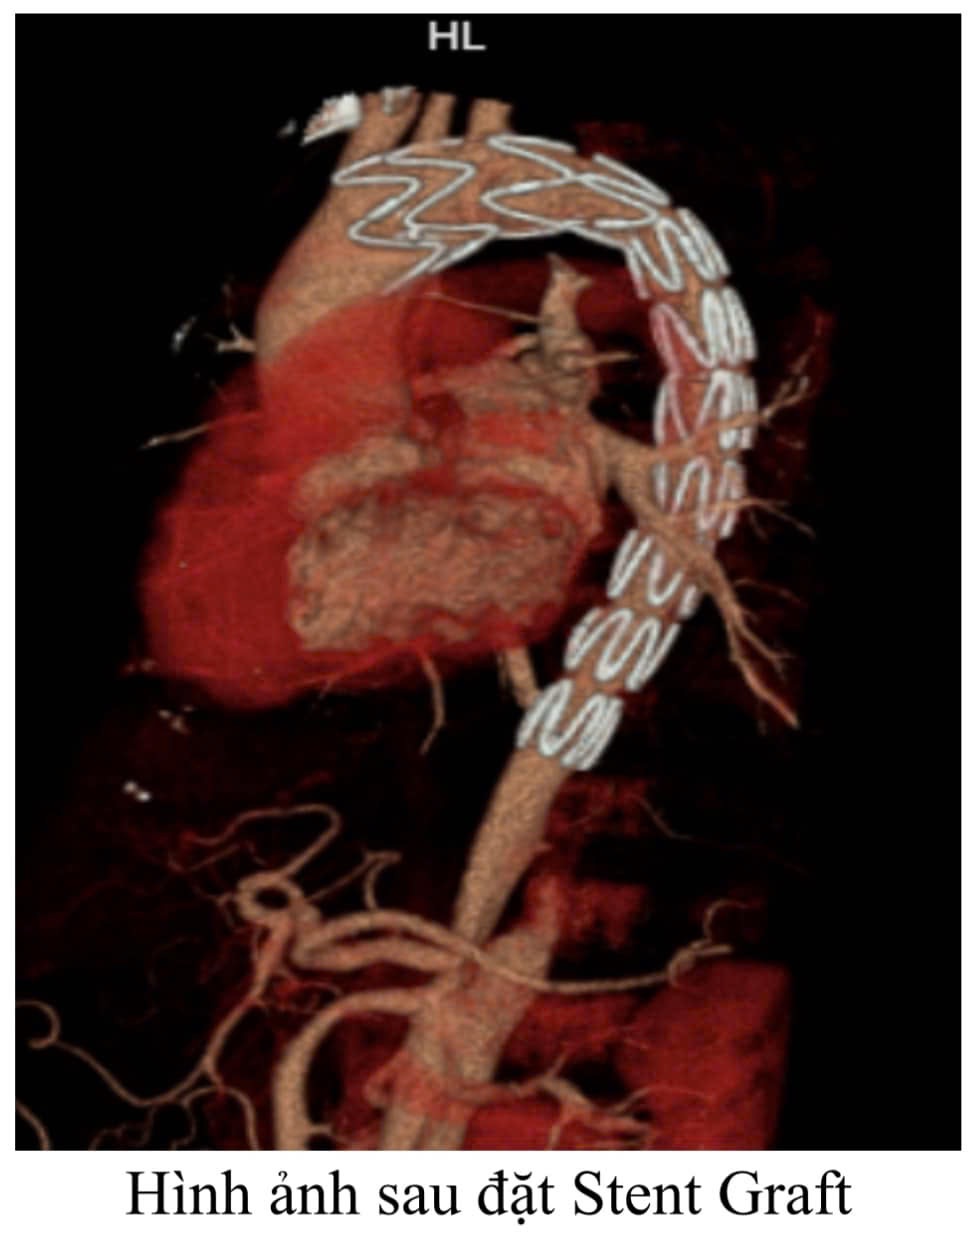

Chỉ trong vòng 1 giờ sau hội chẩn, ê-kíp phẫu thuật mạch máu đã khẩn trương tiến hành phẫu thuật bắc cầu động mạch thành công. Ngay sau đó, Stent Graft đã được các bác sĩ can thiệp cẩn thận đặt từ ngayphía sau đông mạch thân cánh tay đầu xuống động mạch chủ ngực giữ cho động mạch chủ không bị lóc tách, đồng thời nhờ phẫu thuật bắc cầu nối từ trước tưới máu não vẫn được đảm bảo một cách đầy đủ, chỉ cần một vết rạch 2 cm ở vị trí đùi phải, tránh cho bệnh nhân được một cuộc phẫu thuật mở ngực vô cùng nguy hiểm. Sau can thiệp bệnh nhân phục hồi tốt và xuất viện sau 7 ngày điều trị.